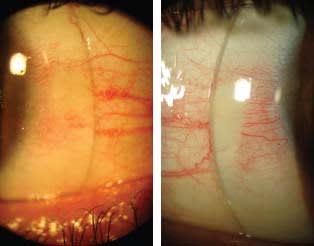

Figure 1. Right eye front view (note redness) and slit lamp 45° cross-section view, turned right.

Figure 1 shows the front and 45-degree cross-section views of his cornea OD, and Figure 2 shows both views OS. The patient was prone to conjunctival hyperemia, which he reported began about one year after undergoing the CXL procedure a few years previously. These images show a less irregular surface OD and a more prolate, ectatic cornea OS.